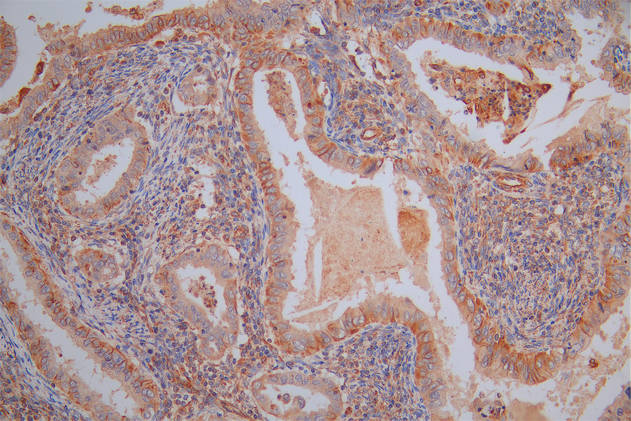

The image on the left is immunohistochemistry of paraffin-embedded Human breast cancer tissue using CSB-PA919263(SPAG4 Antibody) at dilution 1/25, on the right is treated with synthetic peptide. (Original magnification: ×200)

The image on the left is immunohistochemistry of paraffin-embedded Human thyroid cancer tissue using CSB-PA919263(SPAG4 Antibody) at dilution 1/25, on the right is treated with synthetic peptide. (Original magnification: ×200)